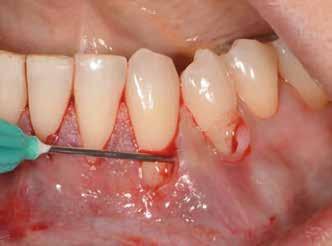

Sebészeti eljárás

Az eljárást helyi érzéstelenítés mellett végeztük (4%-os articaine-hidroklorid 1:100 000 adrenalinnal). Papillakímélő, U alakú palatális bemetszést végeztünk, teljes vastagságú nyálkahártyalebeny preparálás történt, a lebenyt bukkálisan feltekertük (5. ábra). A lebeny bukkálisan feltekert részén de-epitelizációt végeztük el, amellyel kompenzálni tudtuk a bukkális lágyszöveti defektust. Szakaszos előfúrást végeztünk, és a bredent copaSKY 4x10 implantátumot 30 Ncm behajtási nyomatékkal helyeztük be (6. ábra). Az implantátumot 1 mm-re szubkresztálisan helyeztük be, hogy később szélesebb emergenciaprofilt tudjunk kialakítani (7. ábra). Az egyedi ínyformázó úgy készült, hogy kompozitot vittünk fel a titánbázisra, és így formáztuk a lágyszöveteket a transzgingivális gyógyulási fázis során (8. ábra). Az egyéni ínyformázó tulipán formájú, hogy kialakítsa a kívánt emergenciaprofilt. A lágyszövetet feszülésmentesen zártuk #6/0 nem felszívódó, monofil fonallal (Optilene, B. Braun Deutschland; 9. a–b. ábra). Posztoperatív röntgenfelvétel készült, ami alapján az implantátum a szomszédos fogakkal párhuzamos elhelyezést mutatott (10. ábra). Posztoperatív utasításokat adtunk a páciensnek a műtéti terület körüli szájhigiénia fenntartása érdekében. A beavatkozást követő egy héttel a varratokat eltávolítottuk, és a kezelt terület kielégítő gyógyulást mutatott (11. ábra). A 4 hónap utáni késleltetett terhelést a páciens kívánsága szerint terveztük.

1. ábra: Műtét előtti fogászati panorámafelvétel, amelyen a hiányzó felső állcsont jobb első premolárisát és a szabad véggel rendelkező hidat láthatjuk. — 2. ábra: Az implantátum méreteinek megtervezése CBCT-vel. 3. ábra: Bukkális lágyrészdefektus. — 4. ábra: A biológiai szélesség értékelése a vertikális lágyszövetvastagság alapján. 5. ábra: Palatinális „tekercslebeny” – Palatal roll flap. — 6. ábra: Bredent medical copaSKY 4x10 implantátumbeültetés. 7. ábra: Szubkresztális implantátumbeültetés a várható biológiai szélességnek megfelelően.

8. ábra: Egyéni ínyformázó titánbázison, tulipán alakú emergenciaprofillal. — 9. a. ábra: A sebzárás okkluzális nézete.